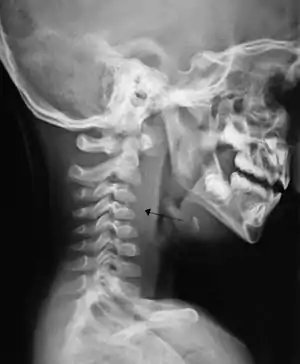

| A lateral cervical spine x-ray demonstrating prevertebral soft tissue swelling (marked by the arrow) as seen in a person with a retropharyngeal abscess. | |

X-ray of the neck often (80% of the time) shows swelling of the retropharyngeal space in affected individuals. If the retropharyngeal space is more than half of the size of the C2 vertebra, it may indicate retropharyngeal abscess.[5]